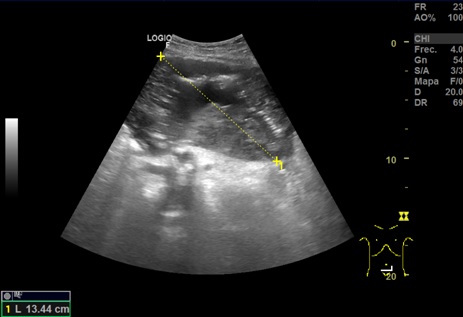

Hallazgos ecográficos: en región umbilical se aprecia una neoformación de contenido heterogéneo de unos 15 cm de diámetro. Imágenes compatibles con Esteatosis hepática. Quistes renales derechos. Esplenomegali.